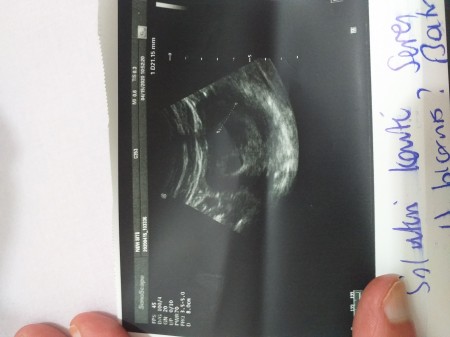

Ultrasonda kesenin boyu nerede yazar. Doktorumuz ultrosonda bebeğimizin boyunun 5 cm olduğunu bununda 12 haftalık bir bebeğe tekabül ettigini söyledi. Arkadaşlar ultrason kağıdında bebeğin boyu ve kilosu yazar mı yazıyorsa hangisi bilgi verir misiniz gebelik haftası 22 6 bu soruya cevap vermek için lütfen giriş yapınız veya kayıt olunuz. Ultrasonda bebeğin kilosu ve boyu nerede yazar. Crown rump length baş popo mesafesi.

Bu süreç içine ultrasonda yapılan bebeğin gerçek şekilde kilo ölçümü değildir. Yalnız ultrasonda bebeklerin kafa çapları karın çevresi bacak boyu ölçümlerinden uzman faydalanır ve tahmini açıdan kilo hesaplaması yapar. Ultrasonda bebeğin kilosu ve boyu nerede yazar. Gebelik ultrasonda ga ne demek.

Humerus uzunluğu kolun uzun kemiği crl. 3 cevap 190 göst. Hamilelikte yapılan ultrason terimleri ve gebelikte ultrason terimleri olarak gebelerin karşılarına çıkan fta ga ga gs bpd aua aua d dr ve bebeğin kalp atış hızını gösteren terimlerin normal değerlerinin bilinmesi tavsiye edilirken buna neden olarak da ultrasonda bebeğin gelişiminin sürekli takip edilmesi gösterilir. Uyluk kemiği uzunluğu 7 ile çarpıp boyu buluruz hl.